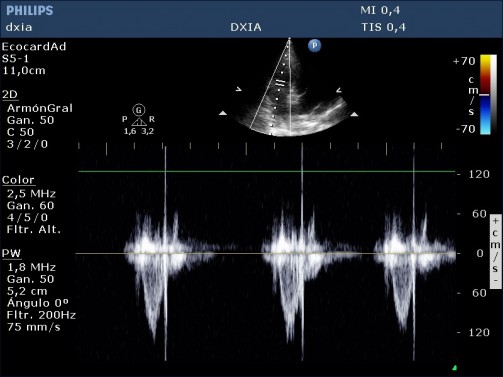

Insuficiencia tricuspídea excéntrica de alta velocidad (4,2 m/seg)

Arteria pulmonar dilatada pero perfil flujo pulmonar debido a:

- Conducto arterioso persistente, aunque no se visualiza, no puede descartarse completamente. Habría que realizar una prueba de contraste.

- Hipertensión primaria congénita por retención de características fetales en la circulación pulmonar.